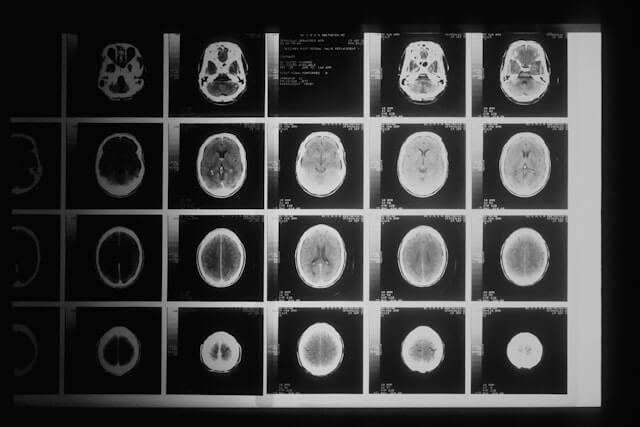

최근 화제의 tvN 화제인 드라마인 '눈물의 여왕'에서 주인공 김지원(홍해인 역)이 희귀병인 '클라우드 세포종'이라는 병을 진단받아 3개월 시한부 선고를 받습니다. 실제로 주인공 김지원님(홍해인 역)이 진단받은 '클라우드 세포종'은 없는 병입니다. '클라우드 세포종'은 '교모세포종'을 모티브로 한 것으로 예상됩니다. 교모세포종(Glioblastoma)은 가장 흔하고 공격적인 형태의 기본 중추신경계(뇌와 척수) 암입니다. 이 질환은 뇌의 지지 조직인 교질에서 발생하며, 성인에서 발생하는 뇌암 중 가장 흔한 형태 중 하나입니다. 그렇다면 '클라우드 세포종'의 모티브가 된 교모세포종의 원인, 증상, 치료방법에 대해서 자세히 알아보도록 하겠습니다.

교모세포종은 뇌암 중에서 가장 흔한 형태 중 하나로, 뇌의 교질 조직에서 발생합니다. 이 암의 증상은 암의 위치, 크기, 그리고 성장 속도에 따라 다양할 수 있습니다. 공통적인 증상으로는 다음과 같은 증상이 있습니다. 첫 번째로 두통입니다. 두통은 특히 아침에 심하거나, 활동으로 인해 악화되는 경향이 있습니다. 두 번째는 구토 또는 메스꺼움입니다. 이러한 증상은 두통과 함께 나타날 수 있습니다. 세 번째는 시력 흐림, 이중 시력, 또는 시력 상실의 시력 문제가 발생할 수 있습니다. 네 번째는 말을 하기 어렵거나 이해하는 데 문제가 생기는 언어장애가 나타날 수 있습니다. 다섯 번째는 집중력 저하, 기억력 감소, 혼란 등의 인지 및 기억 장애가 나타날 수 있습니다. 여섯 번째는 근육 약화, 마비, 조정 장애 등으로 인한 운동 기능 장애가 발생할 수 있습니다. 일곱 번째는 기분 변화, 우울증, 불안 등의 성격 변화 또는 정서적 변화가 나타날 수 있습니다. 마지막으로 갑작스러운 의식 상실, 경련, 또는 감각 이상과 같은 간질성 발작을 경험할 수 있습니다. 이러한 공통적인 증상이외에 교모세포종이 발병한 뇌의 위치에 따라서 다른 증상이 나타나기도 합니다. 먼저 전두엽의 경우 성격 변화, 운동 기능 장애, 계획 및 판단 능력 저하 등이 나타날 수 있습니다. 측두엽은 기억 장애, 시청각 장애, 언어 이해 또는 말하기 문제 등이 발생할 수 있습니다. 후두엽의 경우 시각 장애가 주요 증상입니다. 마지막으로 두정엽의 경우 감각 장애, 공간 감각 상실, 운동 조정 문제 등이 나타날 수 있습니다.

교모세포종의 치료방법은 크게 6가지로 분류됩니다. 첫 번째는 수술적 치료입니다. 수술이 가능한 경우, 교모세포종을 제거하기 위한 첫 번째 치료 방법입니다. 완전히 제거가 어려운 경우에도, 가능한 많이 암 조직을 제거하여 증상을 완화시키고, 다른 치료 방법의 효과를 높일 수 있습니다. 두 번째는 방사선 치료입니다. 수술 후 남은 암 세포를 파괴하거나, 수술이 불가능한 경우 암의 성장을 억제하는 방법입니다. 외부 방사선 치료(EBRT)와 같은 전통적인 방사선 치료뿐만 아니라, 정밀한 방사선을 이용하는 입체 조형 방사선 치료(SRT), 감마나이프 치료와 같은 고정밀 방사선 치료 방법도 있습니다. 세 번째는 화학 요법입니다. 암 세포의 성장을 억제하기 위해 특정 약물을 사용합니다. 테모졸로마이드(Temozolomide)와 같은 약물이 주로 사용되며, 이는 수술 후 및/또는 방사선 치료와 병행하여 사용됩니다. 네 번째는 표적 치료입니다. 암세포의 특정 유전자나 단백질, 그리고 암세포 성장에 필수적인 조직 환경을 대상으로 하는 치료 방법입니다. 이는 정상 세포에는 적은 영향을 주면서 암세포만을 표적으로 합니다. 다섯 번째는 면역 치료입니다. 최근에는 환자의 면역 체계를 활용하여 암 세포를 공격하도록 하는 치료 방법이 연구되고 있습니다. 이러한 치료는 아직 초기 단계이지만, 일부 환자에게 효과적일 수 있습니다. 마지막으로 임상 시험입니다. 기존의 치료 방법 외에도, 새로운 치료법을 시험하는 임상 시험에 참여하는 것도 한 방법입니다. 새로운 약물, 치료 조합, 또는 접근 방식을 탐색할 수 있습니다. 교모세포종은 가장 공격적인 형태의 뇌암 중 하나로, 세계보건기구(WHO)에서 등급 IV로 분류된 고위험군 암입니다. 이러한 고위험군 뇌암은 치료를 진행하여도 빠르게 진행되며, 생존율이 매우 낮습니다. 교모세포종의 5년 생존율은 대략 5%에서 10% 사이입니다. 다른 암에 비하여 매우 낮은 생존율로서, 이 수치는 교모세포종의 공격적인 성격과 치료에 대한 난이도를 보여줍니다. 낮은 생존율이지만 환자의 나이, 건강 상태, 암의 정확한 위치와 크기, 치료를 얼마나 빨리 진행했는지에 따라서 생존율이 달라질 수 있습니다.